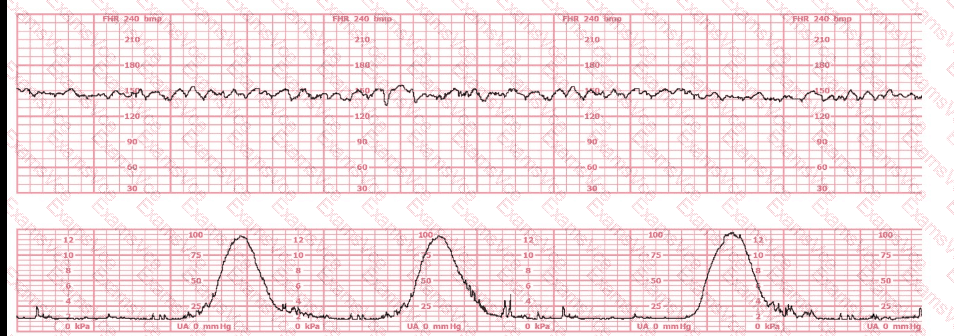

The fetal heart rate (FHR) tracing shown demonstrates a baseline approximately 135–145 bpm with fluctuations of 6–25 bpm, a hallmark of moderate variability. Moderate variability is defined in all NCC-endorsed resources as the normal amplitude range of 6–25 bpm around the fetal baseline.

According to the AWHONN Fetal Heart Monitoring Principles & Practices (2022–2024), moderate variability is considered the single most reliable indicator of adequate fetal oxygenation and intact neurologic pathways, specifically reflecting well-functioning sympathetic and parasympathetic interplay.

The tracing provided does not show the repetitive, smooth, wave-like pattern of a sinusoidal rhythm; nor does it show flattening associated with minimal variability. Instead, it includes continuous beat-to-beat fluctuation within the moderate range, without periods of absent or minimal variability.

Additionally, Miller’s EFM Pocket Guide reiterates that variability between 6–25 bpm is considered the normal (moderate) fetal autonomic response and is not a sinusoidal pattern, which has a fixed amplitude and frequency.

Therefore, based on NCC-standard definitions and the observed amplitude, the correct interpretation is moderate variability.